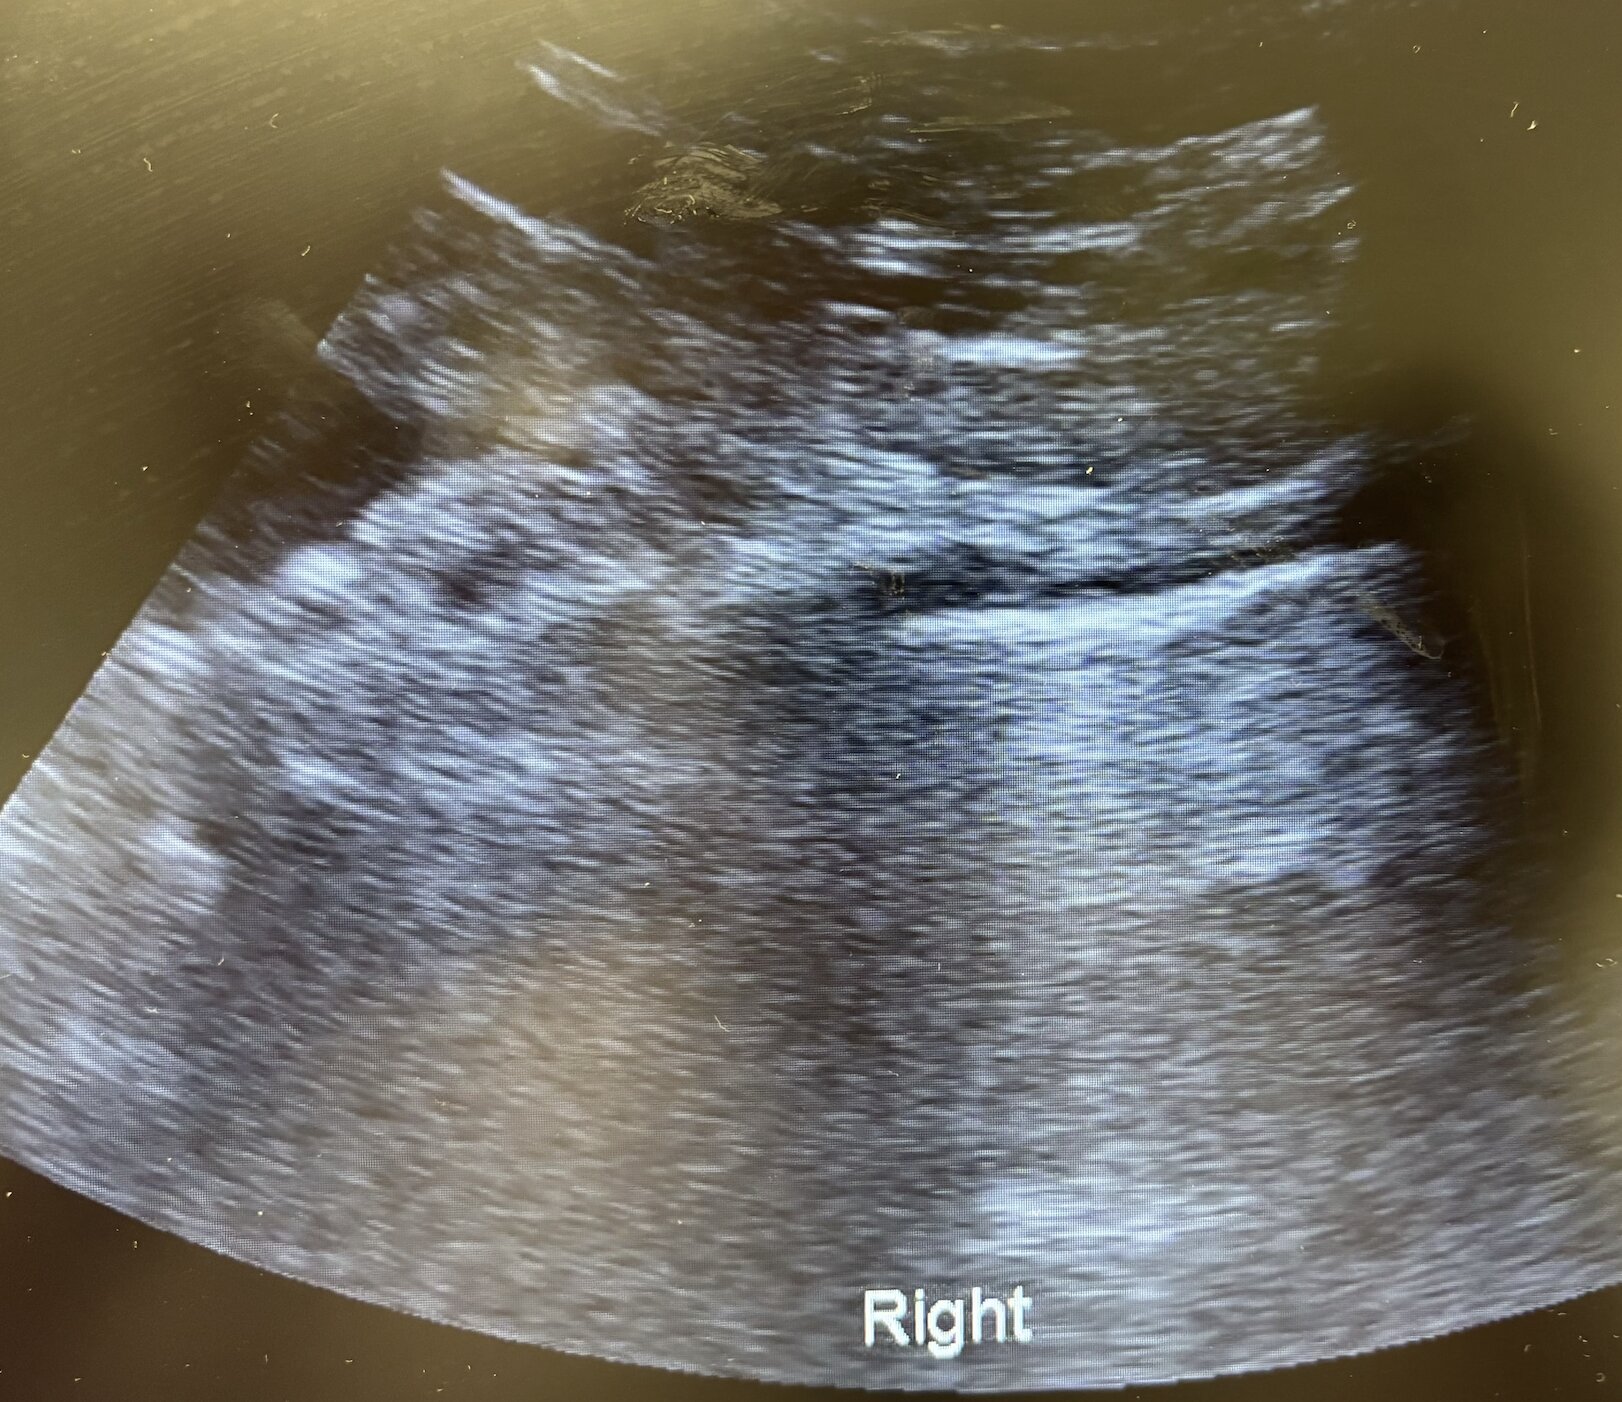

Antes de solicitar otras pruebas complementarias, se decide realizar ecografía clínica pulmonar. Se detecta un patrón intersticial focal en base izquierda, con condensación basal, mínimo derrame pleural y líneas B periféricas. Deslizamiento pleural conservado bilateral.

Sin embargo, la ecografía clínica resultó ser una herramienta fundamental en este caso, proporcionando información diagnóstica rápida, no invasiva y en tiempo real. Y en este caso, fue desde el primer momento, permitiéndonos centrar el caso y conferirle el tiempo y la atención necesaria acorde a la gravedad del mismo.

Como curiosidad, las neumonías suelen presentarse como área hiperecoicas o con sombras acústicas en casos más graves.